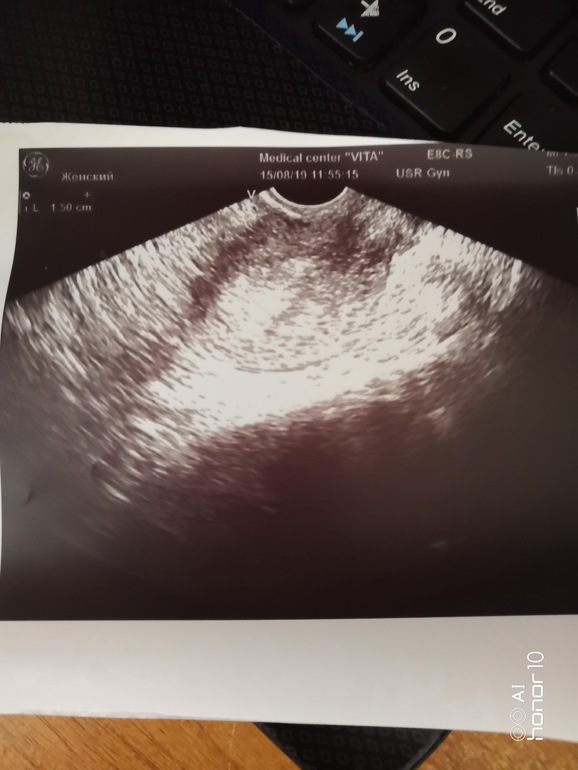

ФолликулометрияВообщем родила я 18 апреля этого года, месячных после этого не было три месяца, за это время эндометрий сильно вырос, вот 10 числа пошли, вызвали Дюфастон ом, с первого дня начала принимать Джес плюс, шли обычно, не сильно, 5 дней, сегодня тишина, сегодня была на УЗИ, эндометрий также толстый, она говорит что если в течение недели не пройдут сильно то будут высасывать(по другому выскабливать) но она сказала сделать ещё тест на всякий случай, говорит что УЗИ может и не увидеть,попробовала сделать, не на первую мочу, вроде ничего нет, вот прилагаю снимки и тест, остался ещё один, с мужем не предохраняемся, так как у меня поликистоз.